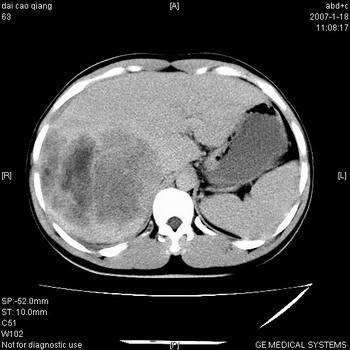

肝右叶巨块型肝癌,伴癌栓形成.

肝右叶巨块型肝癌伴癌栓形成.支持!

符合巨块型肝癌表现:

1、平扫低密度,增强后表现为快进快出。

2、动脉期可见迂曲的动脉供血血管

3、并可见门静脉右支癌栓形成

4、可见假包膜

5、腹主动脉旁结节影,考虑肿大淋巴结。

典型的肝右叶巨块型肝癌破裂、门脉瘤栓形成。

肝右叶巨大不均匀低密度肿块,前缘有假包膜,增强明显的呈快进快出表现,门脉右支有癌栓,病人虽然年轻但还是首先考虑肝右叶巨块形肝癌,病人血象高只能说有合并感染。不支持肝脓肿。